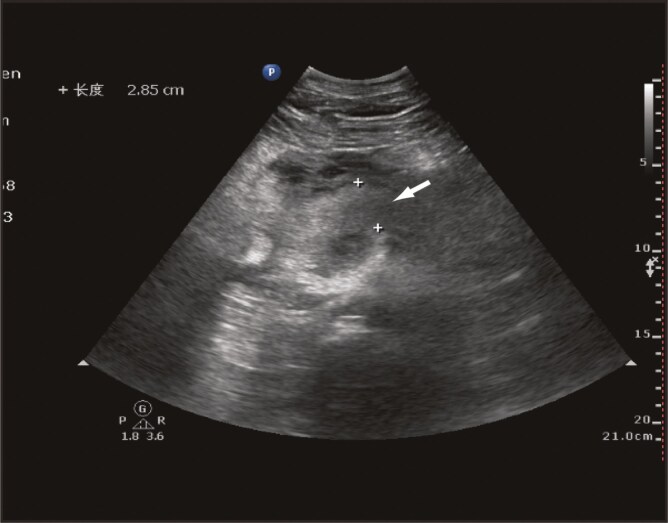

Introduction: Severe acute pancreatitis is a life-threatening condition characterized by systemic inflammatory response syndrome and an increased risk of complications such as venous thrombosis, all of which contributes to a high mortality rate. Heparin resistance, although rare, can lead to ineffective anticoagulation and thrombus formation during unfractionated heparin therapy, complicating management.

Methods: We report a case of heparin resistance in which, despite increasing the unfractionated heparin dosage, the patient's activated partial thromboplastin time remained subtherapeutic.

Results: Laboratory findings indicated normal antithrombin levels but undetectable anti-Xa activity, confirming non-antithrombin-mediated heparin resistance. A multidisciplinary approach led to the successful management of thrombosis with rivaroxaban, resulting in substantial clinical improvement.

Discussion: This case highlights the importance of early recognition and management of heparin resistance in patients with severe acute pancreatitis. Combined monitoring of activated partial thromboplastin time and anti-Xa activity is crucial for optimizing anticoagulation therapy and preventing complications such as deep vein thrombosis.